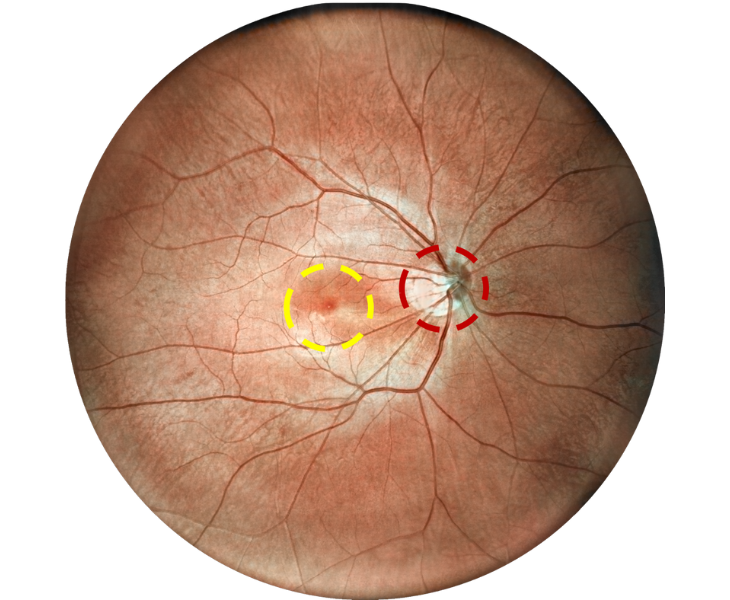

Retina Examination Under Cataracts

Examining fundus diseases through cataracts is a crucial topic in ophthalmology. Traditional fundus cameras cannot see through cataracts to capture fundus conditions. However, our DF600 scanning laser ophthalmoscope can penetrate moderate cataracts, providing a glimpse into the fundus and offering greater convenience for fundus examinations in patients with cataracts.

High blood pressure, venous obstruction, and bleeding